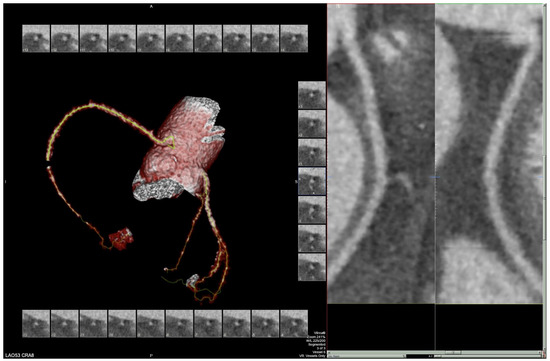

The patient’s EKG (Figure 1) on admission demonstrated a left bundle branch block pattern not previously documented in the patient’s medical history. Additionally, chest radiography (Figure 2) and computed tomography (Figure 3) on admission demonstrated cardiomegaly. Transthoracic echocardiography was technically difficult but demonstrated severe left ventricular systolic dysfunction with an ejection fraction of <15%. Initial brain natriuretic peptide (BNP) on admission was 981 pg/mL. The patient was recommended to start on 25 mg metoprolol succinate, 81 mg aspirin, 5 mg Lisinopril, and 40 mg atorvastatin. Metoprolol and Lisinopril were started initially as therapy for newly diagnosed DCM whereas aspirin and atorvastatin were started before coronary artery disease was ruled out with cardiac CT angiography (Figure 4 and Figure 5). The patient developed electrolyte abnormalities after the first day of treatment, including hypomagnesemia and hyperkalemia, likely secondary to longstanding untreated fluid overload due to heart failure. In response to this and the noted acute kidney injury, Lisinopril was discontinued. Additionally, the patient’s ALT and AST levels rose dramatically. Gastroenterology evaluation was obtained due to elevated liver function tests with a differential diagnosis of shock liver vs. Budd Chiari syndrome; therefore, N-Acetyl cysteine was prophylactically used and improved liver function over the subsequent week and atorvastatin was discontinued. The patient was continued on heart failure management. A repeat echocardiogram showed an improved ejection fraction of 25% with left ventricular dilation (left ventricular internal dimension in diastole 5.65 cm; left ventricular internal dimension in systole 4.95 cm; relative wall thickness 0.34; left ventricular mass 218.2 g; left ventricular mass index 131.8 g/m2) and no left ventricular thrombus noted. Additionally, mildly reduced right ventricular systolic function was noted.

Figure 4. Segment of cardiac CT angiography demonstrating cardiomegaly and no coronary artery disease.

Figure 5. Segment of cardiac CT angiography demonstrating cardiomegaly and no coronary artery disease.